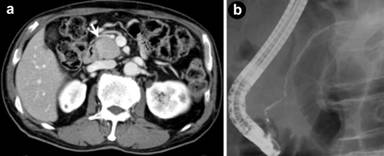

At consultation to our division, serum tests indicated increased level of amylase (160 IU/L; reference range: 43-116 IU/L) and HbA1c (12.0%; reference range: 4.3-5.8%). Serum IgG and IgG4 were elevated to 1,920 mg/dL (reference range: 870-1,700 mg/dL) and 123 mg/dL (reference range: 4.8-105 mg/dL), respectively. The titer of serum antinuclear antibody (ANA) was also high (positive at x80 dilution). At first, the patient hesitated to undergo endoscopic examinations, because of his faint abdominal symptoms and warfarin treatment for his post-myocardial infarction status. However, in May 2007, abdominal CT revealed that the pancreatic lesion had expanded toward the head region (Figure 1a), and was accompanied by a faintly enlarged lymph node (less than 10 mm) in the pelvis, so the patient agreed to further examinations. Endoscopic retrograde cholangiopancreatography (ERCP) revealed a stenosis of the distal bile duct, and diffuse, irregular narrowing of the main pancreatic duct (Figure 1b). 18F-fluorodeoxy glucose positron emission tomography (FDG-PET) showed a faint accumulation of FDG at the pancreas (SUV max: 3.1), multiple mediastinum lymph nodes, and right-upper gingiva (gingivitis). Endoscopic ultrasound-guided fine-needle aspiration biopsy (EUS-FNAB) from the pancreatic head revealed no malignancy. These findings led to diagnosis of autoimmune pancreatitis with sclerosing cholangitis, based on the Japanese criteria [3]. Oral intake of prednisolone was initiated at a dose of 40 mg/day and then tapered off at the recommended pitch. Pancreatic enlargement was resolved and glucose tolerance was improved (HbA1c: 7.4%) over the next three months.

Figure 1. Image findings at the initial diagnosis of autoimmune pancreatitis. a. Computed tomography showed slightly low-dense and enlarged pancreatic head (arrow). b. Endoscopic retrograde pancreatography demonstrated a diffuse, irregular narrowing of the main pancreatic duct. |